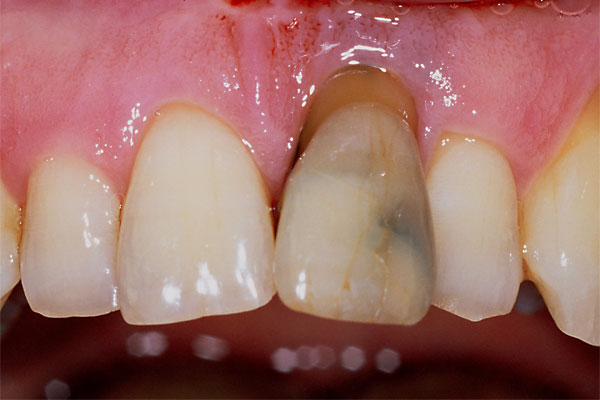

Fall: Einzelzahnlücke nach Zahnextraktion

![]() |